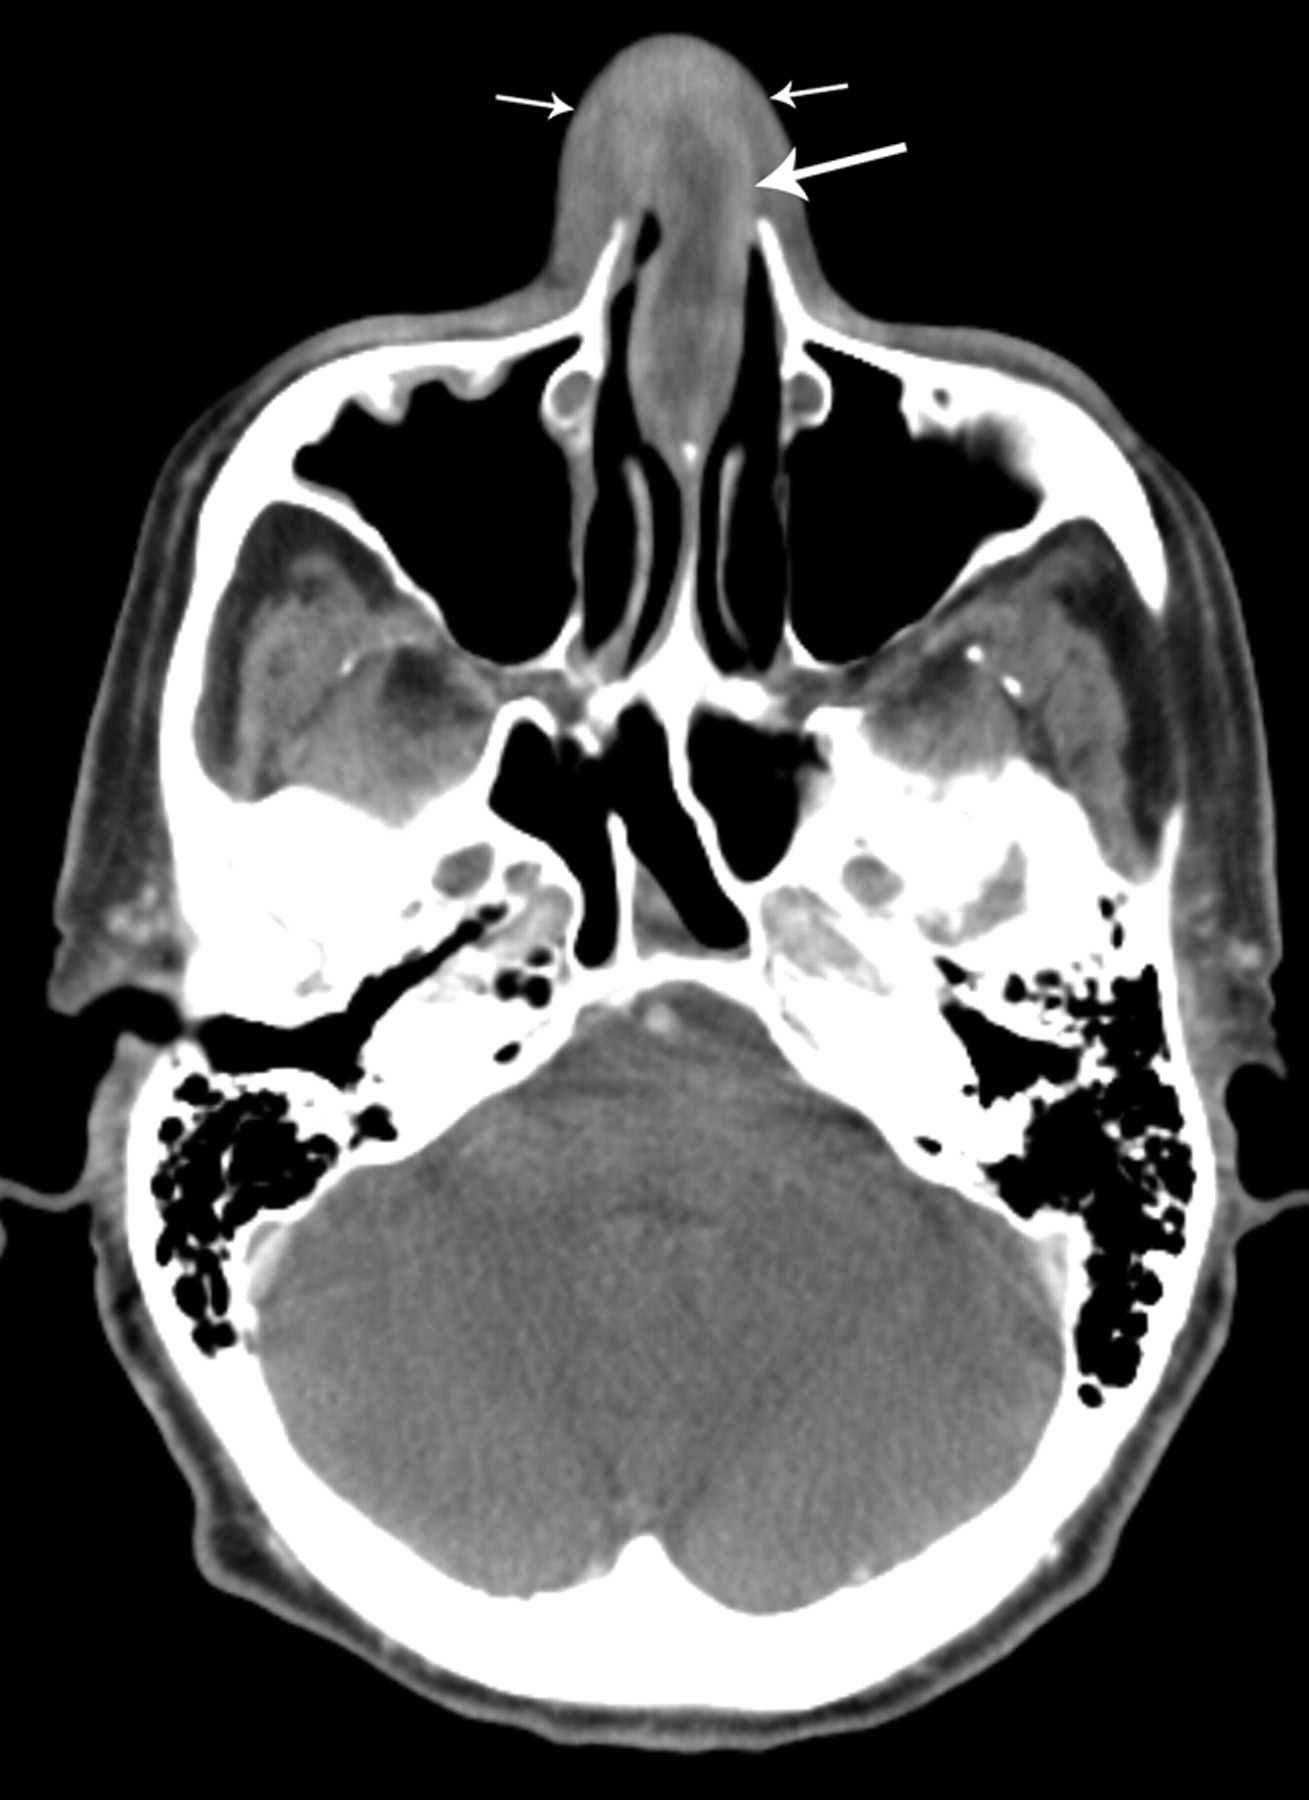

Nasal Septal Hematoma

Understand the urgent risks of a nasal septal haematoma, a serious complication requiring prompt medical intervention. Learn to recognize symptoms like nasal obstruction and pressure following trauma, and discover why emergency surgical drainage is essential to prevent permanent cartilage damage and structural nasal deformity. Protect your health with this critical guide to timely diagnosis and effective treatment options.